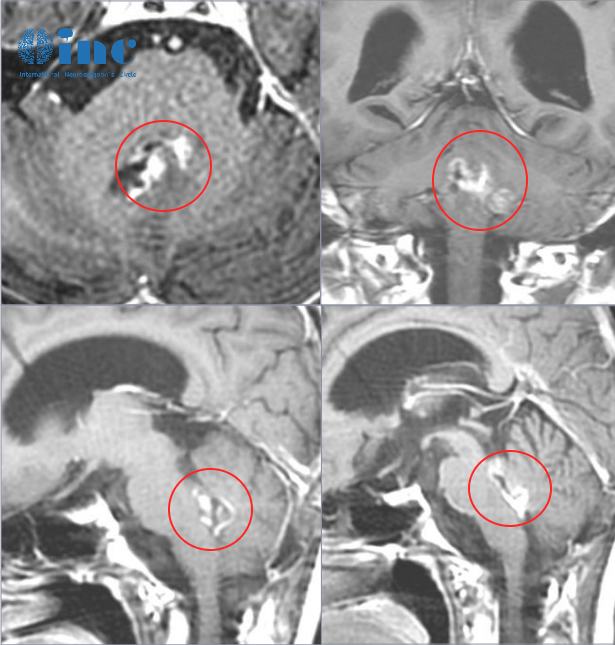

脑干低级别胶质瘤,2个月迅速生长6mm

21岁的张远早在6年前就检查出无症状脑积水,当时由于...

脑胶质瘤会不会停止生长?看脑干中脑胶质瘤2个月迅速增大

21岁的张远(化名)是一名高校研究生,早在6年前就检...